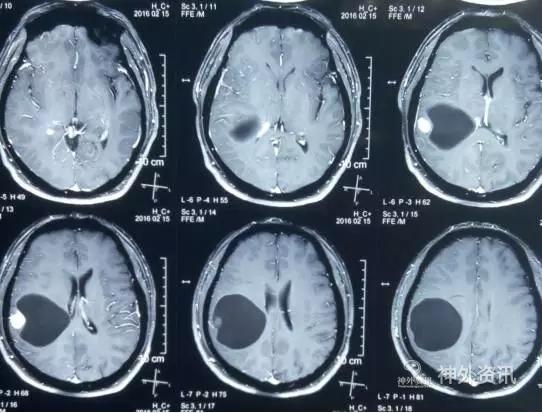

术后患者恢复良好,神志清,精神佳,四肢肌力V级,肌张力正常,病理征(-)。术后CT(图5)MRI(图6)未见血肿,肿瘤全切。

图5. 术后2小时CT。

图6. 术后48 小时 MRI (增强)。